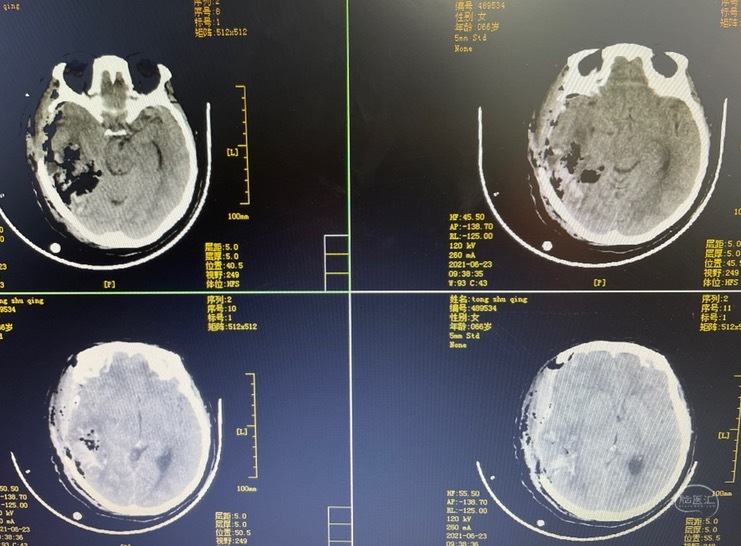

术后半年来院行颅骨缺损修补

钛网颅骨修补

是目前最常用的修补材料